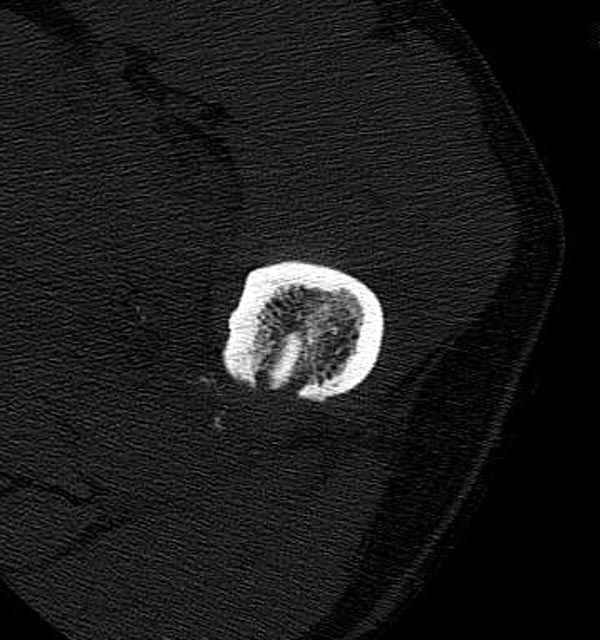

Больной с огнестрельным переломом бедра с вовлечением около 15% медиального кортекса, входное отверстие около 1 см в диаметре; стабильный, без сосудистых и неврологических признаков.

Входные маленькие отверстия от ранении просто игнорируются, никаких дренажей, как любое колотое ранения, они закрываются и были случаи через месяц. Конечно, ведется профилактика открытых ранении: сыворотки и т.д., но еще самое главное уделяем профилактике образования перелома из-за стресса в результате дефекта кортикального слоя.

Литературные данные о влиянии кортикального дефекта на стрессовые переломы в длинных трубчатых костях в основном встречаются в онкологии, например кортикальный дефект более 50% имеет больше шанса стрессовых переломов, чем в нашем случае.

Учитывая, что больной получил травму не во время визита в церковь, и он является одним из представителем 40 миллионного “outstanding itizen”, без медицинской страховки, без работы в свои 39 лет, и без надлежающей ортопедической дисциплины у которого отсутсвует страх стрессового перелома, было рекомендовано оперативное лечение: профилактическое антеградное интрамедуллярное штифтование.

Методика штифтования при отсутствии большой зоны перелома как при онкологических профилактических штифтованиях, расверливание интрамедуллярного канала проводим с предварительным наложением дополнительного дренажного отверстия в дистальном отделе бедра (в данном случаи в канале оставили 6.5 мм канюлированный шуруп), иначе при создании давления в канале во время сверления имеется опасность эмболизации легочной артерии тромбом.